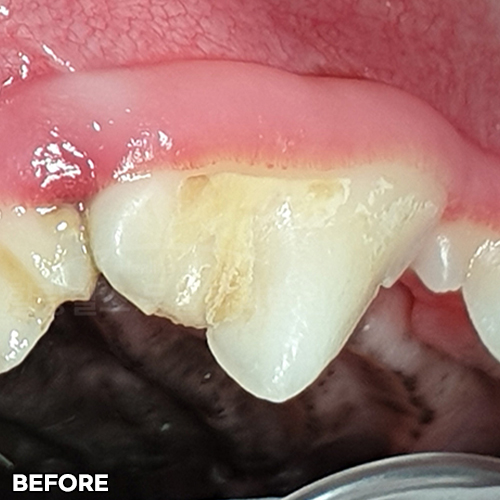

[깨진 강아지 치아 레진치료 전후]